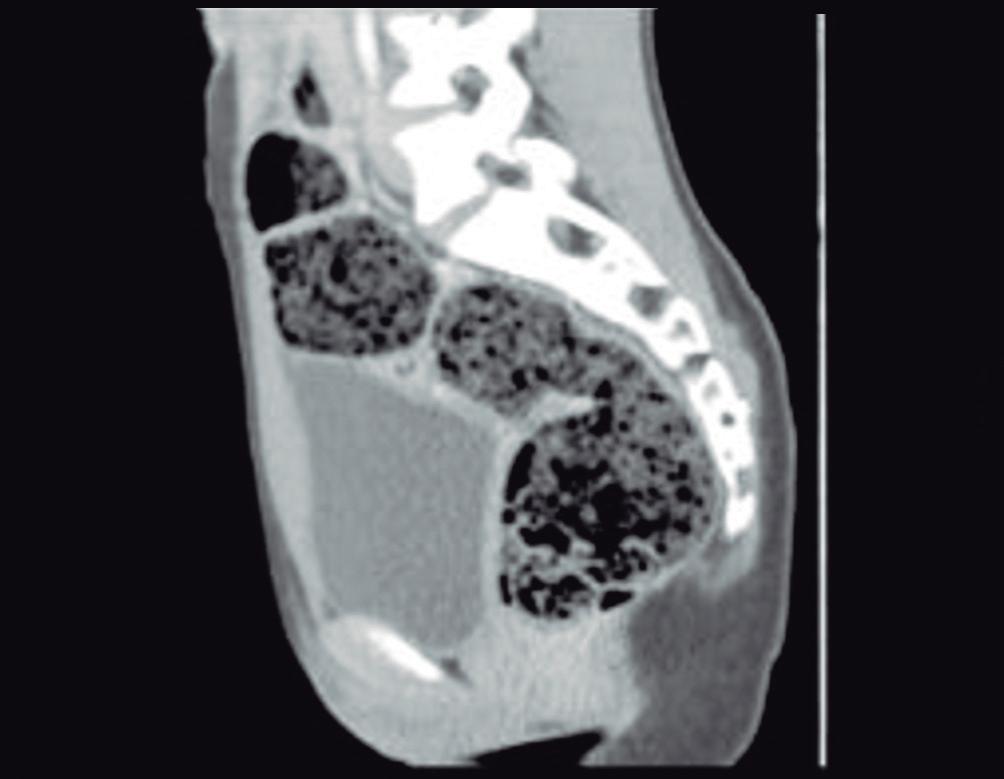

(Figura 1) En los hemangiomas de mayor tamaño el pasaje del contraste al centro de la lesión toma más tiempo e incluso no ocurre en aquellos más voluminosos.

A, en fase arterial; B, y en fase de equilibrio; C, que muestran una lesión de contornos lobulados y bordes netos en el lóbulo hepático derecho que presenta refuerzo globular, progresivo e isodenso con las estructuras vasculares.